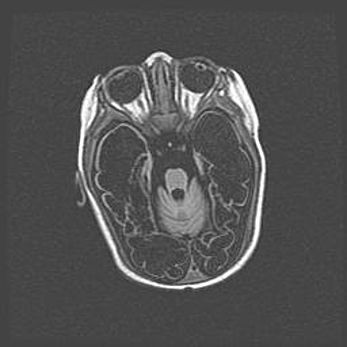

Наружная гидроцефалия с возможной атрофией височных областей.

Возраст: 28 дней

Вес: 3670 г

Пол: мужской

Окружность головы: 38 см

Срок гестации: 40 недель

Гидроцефалия головного мозга у новорожденных – это заболевание, которое характеризуется скоплением избыточного количества спинномозговой жидкости в желудочковой системе головного мозга в результате затруднения её перемещения от места выработки к месту поглощения в кровеносную систему или вследствие нарушения абсорбции. При открытой наружной форме гидроцефалии у новорожденных расширяются и переполняются субарахноидные пространства.

При нормотензивных  формах,  которые,  как  правило,  являются  следствием  перенесенных ишемических  повреждений  паренхимы  мозга,  возможно  сочетание микроцефалии  с нормотензивной гидроцефалией. В основе данных изменений лежит атрофия больших полушарий с преимущественной  локализацией  в  лобно-височных  областях.